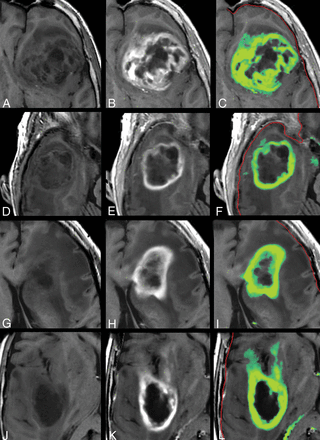

In Fig 4, the tumor in Fig 2 is zoomed-in. The native and post-GBCA T1-weighted images are shown as well as the ROI drawn by the radiologist. In Fig 4D, the synthetic R1 enhancement map is shown as a green overlay where full color corresponds to a dR1 of 1 second−1. At various places, low-intensity enhancement in the range 0.2–0.5 seconds−1 is observable outside the high-intensity enhancing tumor and drawn ROI. On average for all patients, 35.8% of the pixels touched by the drawn ROI lines had values above 0.2 seconds−1 for the synthetic R1 enhancement map and even 50.3% for the subtraction R1 enhancement map. When the ROI line was expanded with an additional margin of 1 or 2 mm, this percentage reduced to 8.0/17.4% and 2.3/8.6%, respectively (Table 2).

Zoomed part around the tumor displayed in Fig 2. Synthetic T1-weighted imaging using native data (A), synthetic T1-weighted imaging using post-GBCA data (B), the ROI line as drawn by a neuroradiologist to encapsulate the border of the enhancing tumor (C). D, Synthetic R1 enhancement map shown as a green overlay on the synthetic T1-weighted image in which full color corresponds to dR1 = 1.0 seconds−1. The minimum enhancement was set at dR1 = 0.2 seconds−1. Some low-intensity enhancement is visible outside the yellow ROI. The red line indicates the edge of the intracranial volume.

In 10 of 14 patients, >1 mL of tissue was found in the synthetic R1 enhancement images with an enhancement of >0.2 seconds−1 outside the drawn ROI. The mean additional tumor volume for all patients was 1.71 ± 1.28 mL, with a maximum of 4.3 mL. In comparison, the mean tumor volume within the ROIs was 63.5 ± 44.4 mL (range, 9–134 mL). More examples of the synthetic R1-enhancement maps are provided in Fig 5.

Other examples of the synthetic R1 enhancement map and low-intensity enhancement at the edges of high-intensity enhancement in gliomas. Left: native synthetic T1-weighted image. Center: post-GBCA synthetic T1-weighted image. Right: synthetic R1 enhancement map as a green overlay. The color indicates a range of dR1 of 0.2–1.0 seconds−1. The red line indicates the edge of the intracranial volume.